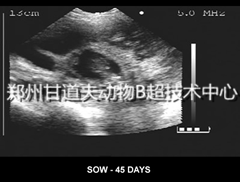

在养猪生产中,虽所有养猪者都知道给猪水喝,但却常常忽视水的重要性,不重视水的质量和给量。常给不清洁或不符合饮用标准的水;或给水不足,导致猪消化、吸收、生长、繁育以及生命都受到影响,导致疾病频频发生。有的养猪户为节约成本,用附近扔死猪、死鱼又排污处的池塘水或臭水沟的水来冲洗猪舍,甚至作为猪的饮用水。如此差的水质,易引发各种各样的疾病,出栏率不高,饲料经销商反映配置了进口猪用B超后客户收益却增加啦养殖户最终为此付出代价。也有的养猪户或猪场没有自由饮水设备,缺乏对水重要性的意识,为节省劳动力,只给猪喂料时加点料水而已,导致猪的供水量极为不足,严重影响猪的生长发育。 母猪的一个发情周期通常为18天左右,如果母猪成功受孕后,精子和卵子形成的受精卵,就会构成一个胚胎,猪为多胎动物,胚胎经过一个周期发育,就会在子宫内成为一个孕囊,在掌握熟练的B超操作技术和高性能的猪用B超协助下,最早可在18天观察到孕囊,但由于此时孕囊很小,不容易被检测到,所以我们建议最好在23天以上检测怀孕,以25~45天最佳。

超声断层显像法(Ultrasonotomography),辉度调制型超声诊断法,简称B型(B-mode)超声或B超。B型超声诊断法是将回声信号以光点明暗,即灰阶(Gray scale)的形式显示出来。光点的强弱反应回声界面反射和衰减超声的强弱。这些光点、光线、光面构成了被探测部位二维断层图像或切面图像,这种图像称为声像图(Sonography)见下图。 是由多元探头,主控电路,逻辑电路,发射电路,接收电路,偏转电路,甘道夫进口猪用B超品牌生产厂家www.gandaofo.com www.gandaofo.cn 淘宝店铺 https://dwbc.taobao.com/ https://shop343625326.taobao.com/ 补偿电路,时标电路及显像管等组成,多元探头上有一排的压电晶片(即晶片阵元),经主控电路,逻辑电路和发射电路控制,按一定的规律有序的发射出一排超声波,饲料经销商反映配置了进口猪用B超后客户收益却增加啦当超声在介质中传播遇到声学界面反射时,回声信号经接收电路,在时标电路,补偿电路等控制下,使X,Y扫描电路工作,将回声信号按一定的规律,根据回声的强弱,坐标有序地在显象管荧光屏上显现出探查部位光点明暗的声象图。产生由点,线到面构成的二维超声切面图。